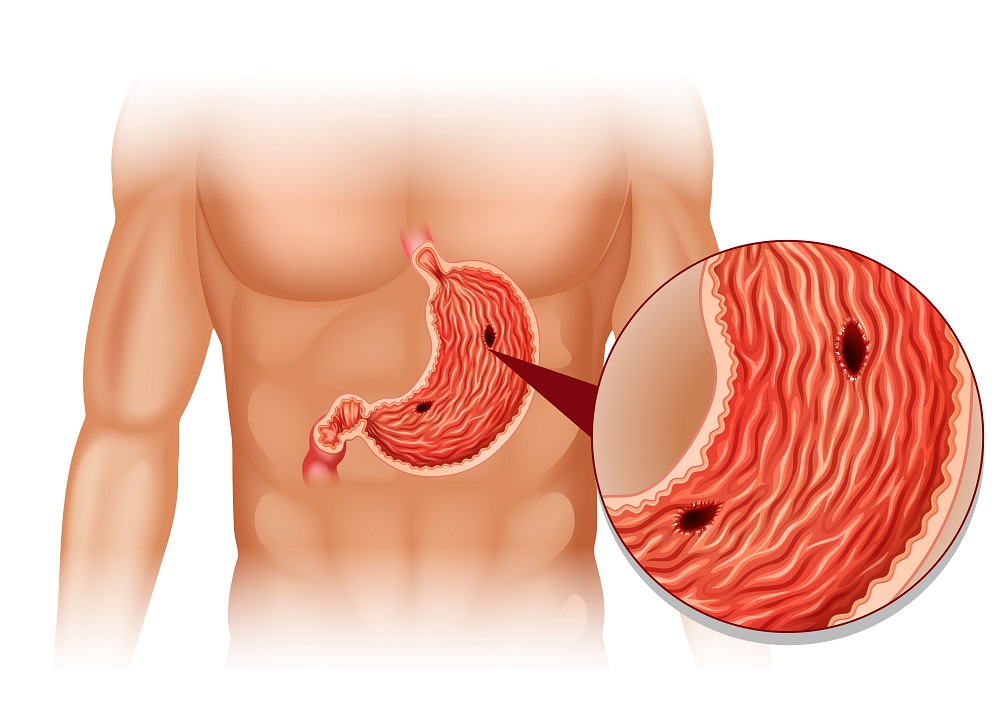

Информация и фотографии о хроническом гастрите и дуодените